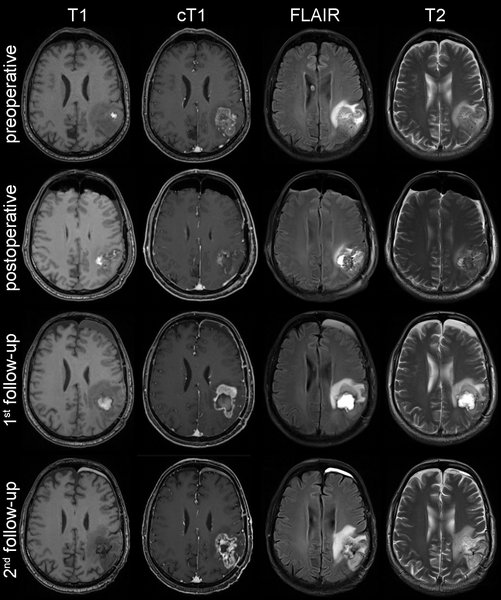

Ein Team vom Universitätsklinikum Heidelberg (UKHD) und vom Deutschen Krebsforschungszentrum (DKFZ) hat ein neues Verfahren zur automatisierten Bild-Analyse von Hirntumoren entwickelt. In ihrer aktuellen Arbeit zeigen die Autoren, dass anhand von Standard-Magnetresonanztomographien (MRT) sorgfältig trainierte maschinelle Lernverfahren das Therapieansprechen bei Hirntumoren verlässlicher und präziser wiedergeben als etablierte radiologische Verfahren – und damit einen wertvollen Beitrag zu einer individuell angepassten Behandlung der Tumoren liefern. Darüber hinaus ist das validierte Verfahren ein wichtiger erster Schritt zur automatisierten Hochdurchsatzanalyse medizinischer Bilddaten von Hirntumoren.

Anhand einer Referenzdatenbank mit MRT-Untersuchungen von knapp 500 Hirntumorpatienten des Universitätsklinikums Heidelberg erlernten die Algorithmen unter dem Einsatz künstlicher neuronaler Netzwerke die Hirntumoren automatisch zu erkennen und zu lokalisieren. Außerdem wurden die Algorithmen darauf trainiert, die einzelnen Bereiche (kontrastmittelaufnehmender Tumoranteil, peritumorales Ödem) volumetrisch zu vermessen und das Therapieansprechen präzise zu beurteilen.

Die Ergebnisse wurden in Kooperation mit der European Organisation for Research and Treatment of Cancer (EORTC) umfassend validiert. „Die Auswertung von über 2.000 MRT-Untersuchungen von 534 Glioblastom-Patienten aus ganz Europa zeigt, dass unser computerbasierter Ansatz eine zuverlässigere Beurteilung des Therapieansprechens ermöglicht, als es mit der herkömmlichen Methode der manuellen Messung möglich wäre. Wir konnten die Verlässlichkeit der Beurteilung um 36 Prozent verbessern. Das kann für die auf Bildgebung basierende Beurteilung der Wirksamkeit einer Therapie in klinischen Studien von entscheidender Bedeutung sein. Auch die Vorhersage des Gesamtüberlebens war mit unserem neuen Verfahren exakter möglich“, erklärt Kickingereder.